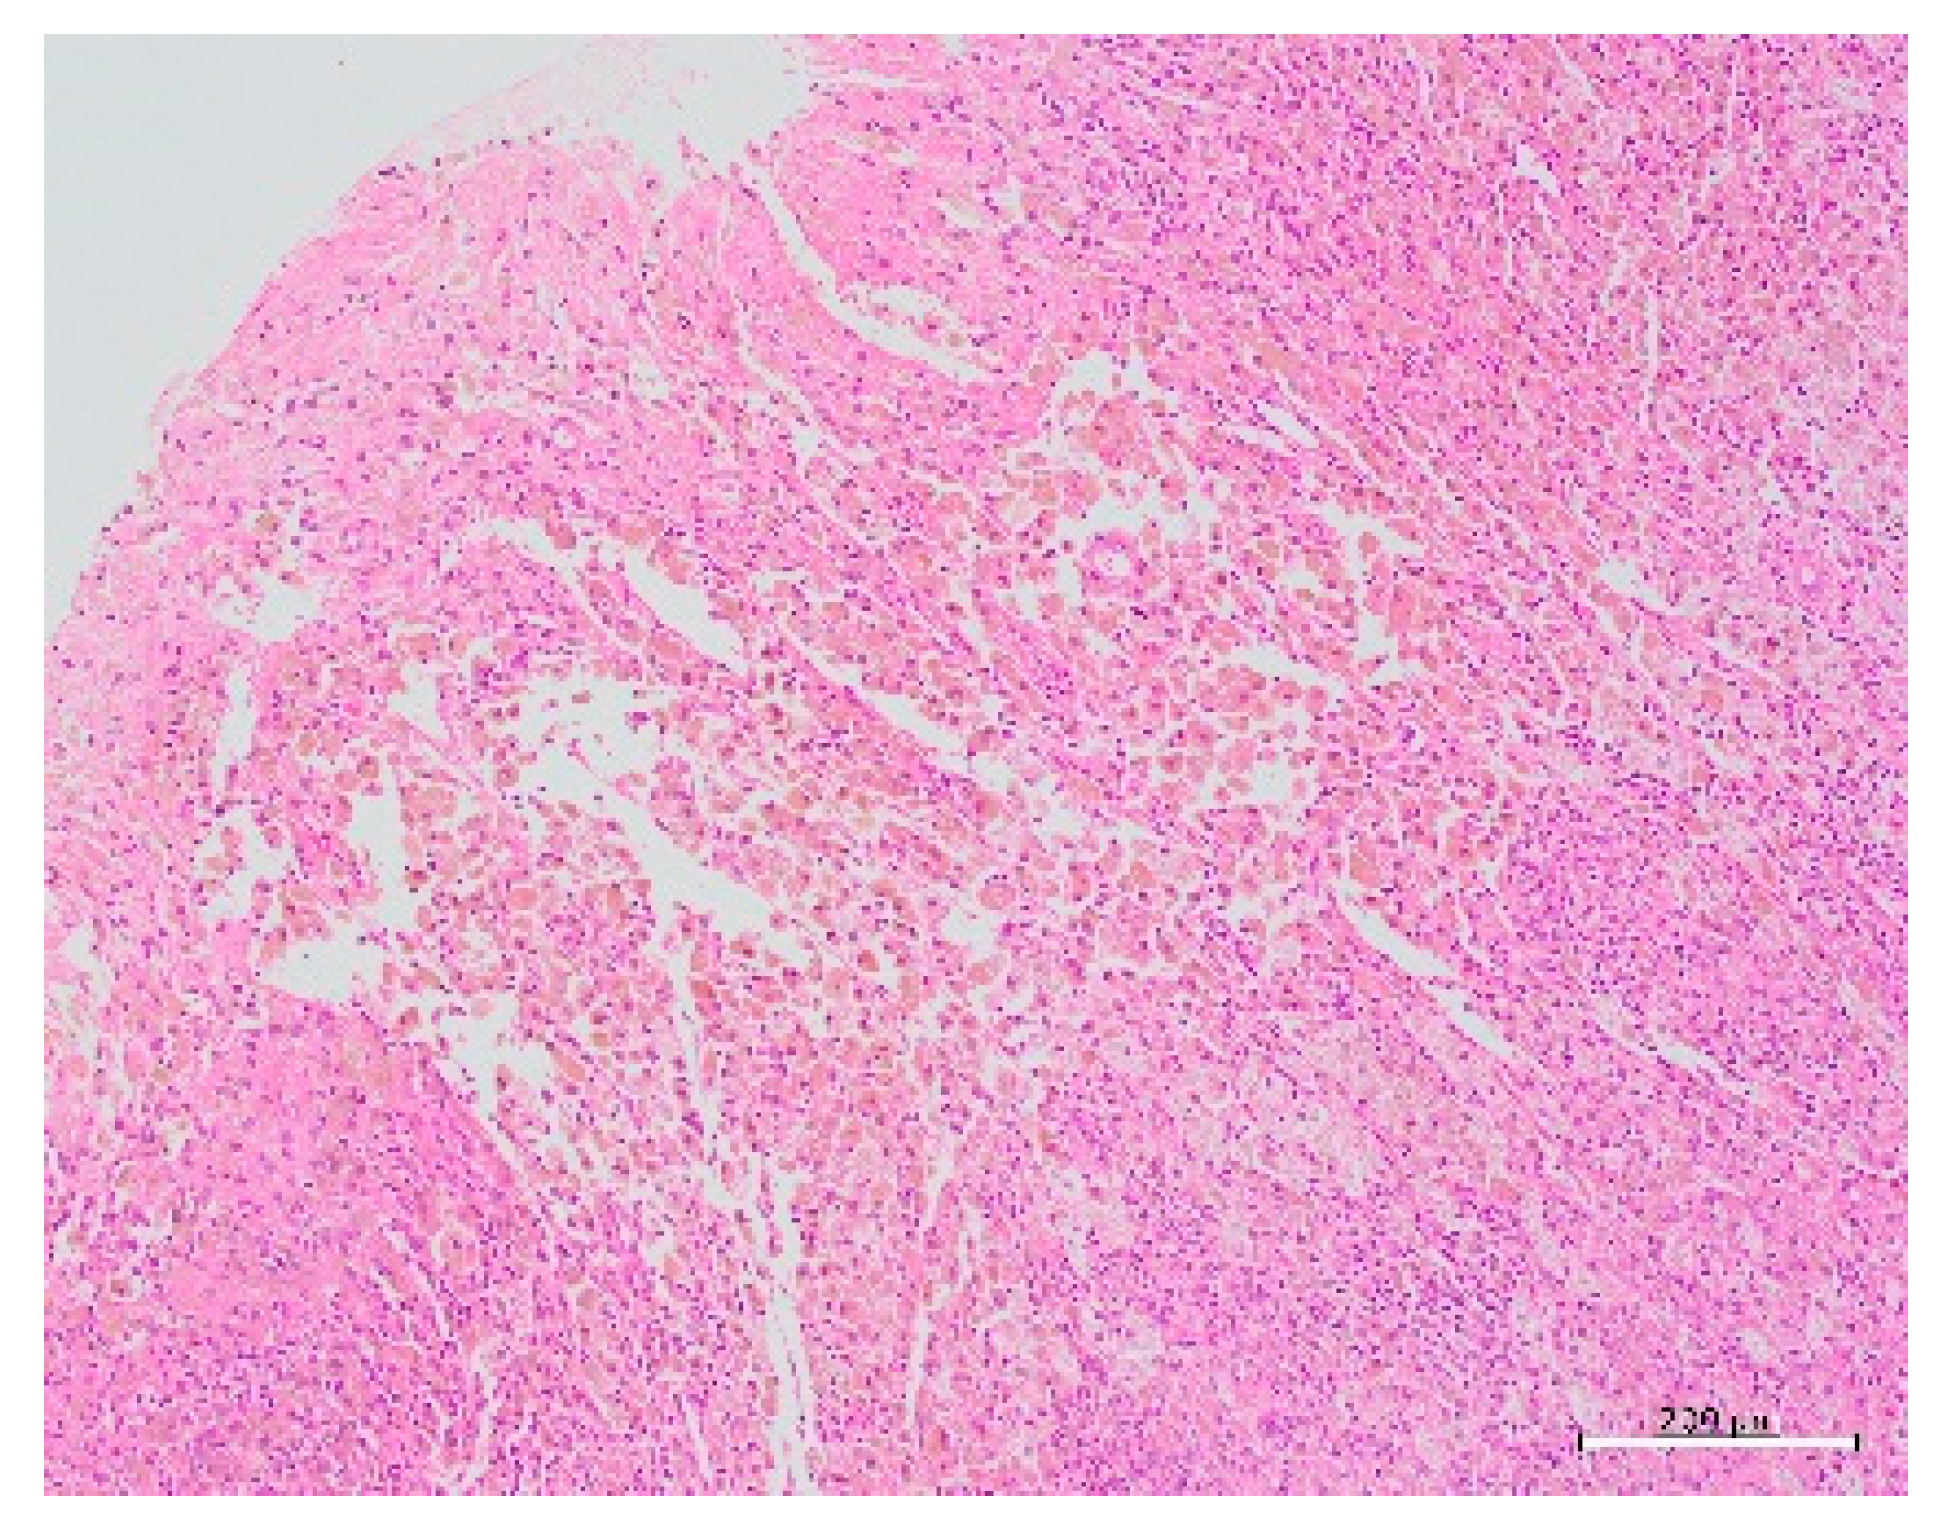

| This case | 22 | 0 | 0 | 15 | 36 | L | 51.9 | None | CT, MRI: None | Laparoscopy | 3 cm, lateral, left side | Harmonic Scalpel, scissors forceps | 2 layers using 0 PDS | 14 | 69 | few | 2 | Present study |